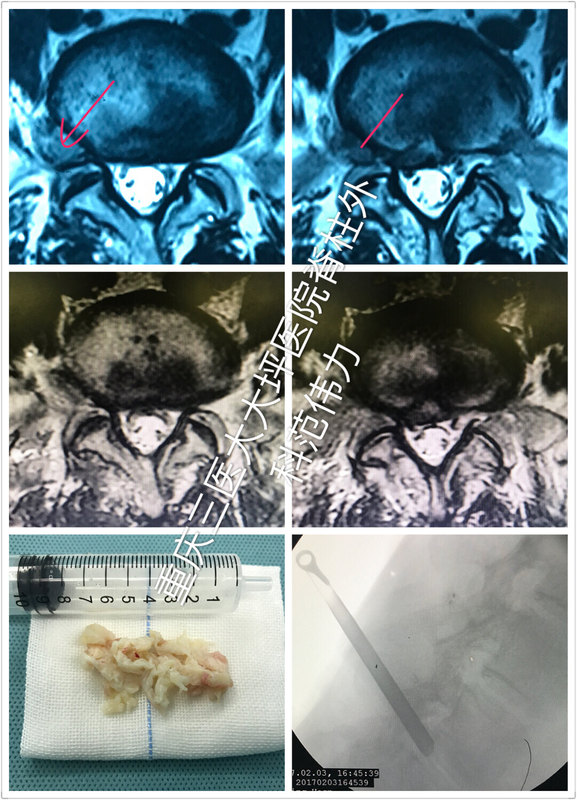

男性,56歲腰椎間盤(pán)突出患者,腰5骶1極外側(cè)椎間盤(pán)突出,壓迫了右側(cè)腰5神經(jīng)根,右小腿外側(cè)疼痛,大腳趾麻木疼痛。在當(dāng)?shù)蒯t(yī)院接受椎間盤(pán)射頻消融術(shù)后第二天疼痛難忍無(wú)法下床活動(dòng)。輾轉(zhuǎn)來(lái)我院就診(第三軍醫(yī)大學(xué)大坪醫(yī)院脊柱外科) 極外側(cè)椎間盤(pán)突出癥是椎間孔鏡手術(shù)的極佳適應(yīng)癥。這位患者手術(shù)用時(shí)約半小時(shí),不需導(dǎo)尿,當(dāng)即癥狀緩解,六小時(shí)后自行下地活動(dòng)。第二天復(fù)查核磁后出院。效果杠杠的(其實(shí)我們的病人效果基本都杠杠的)。[嘻嘻] 脊柱微創(chuàng)范醫(yī)生團(tuán)隊(duì),為您提供最適合的脊柱疾病解決方案。助您擁有健康小腰!